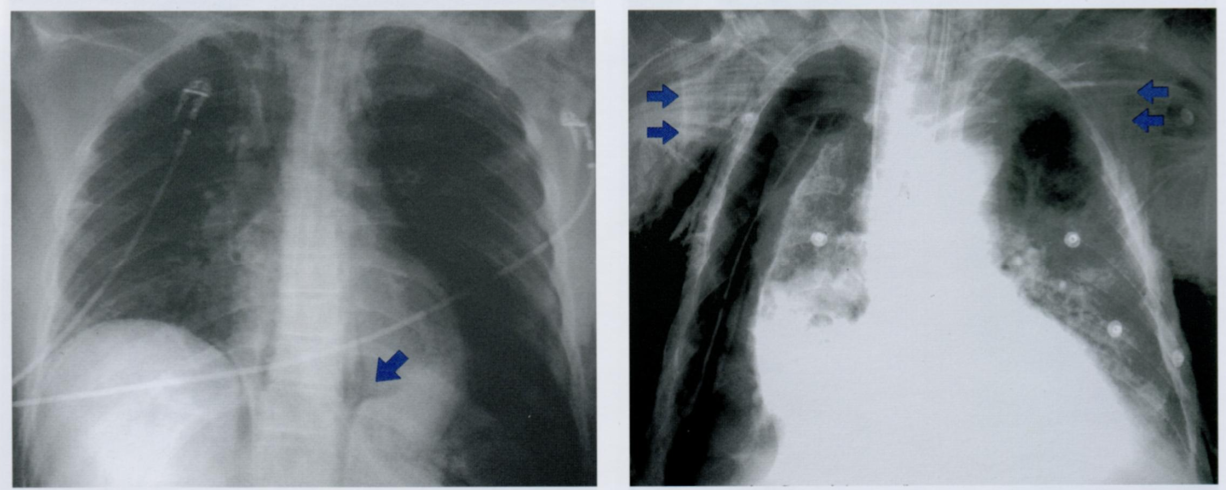

Как вы оцените объект, отмеченный стрелкой?

Это очередной источник недоразумения, который может быть интрепертирован, как внутрилегочное образование. Этот соски.

В некоторых случаях после пометки сосков накожными металлическими маркерами выполняется контрольная рентгенограмма (фото ниже).

Как Вы оцените объекты отмеченные на снимке, принимая во внимание, что клиника и снимок никак нет коррелируют?

ЗПП - задняя прямая проекция и БП - боковая проекция

То есть, вероятнее всего, это артефакты. Какие?

Стрелками на первом снимке отмечены заплетенные и распущенные волосы, которые приводят к появлению артефатков, которые имитируют восходящий пневмомедиастинум или подкожную эмфизему.

На втором снимке мы видим ампутационную культю руки в БП, которая выглядит как веслообразное затемнение на уровне проекции верхнего средостения. Может имитировать новообразование.